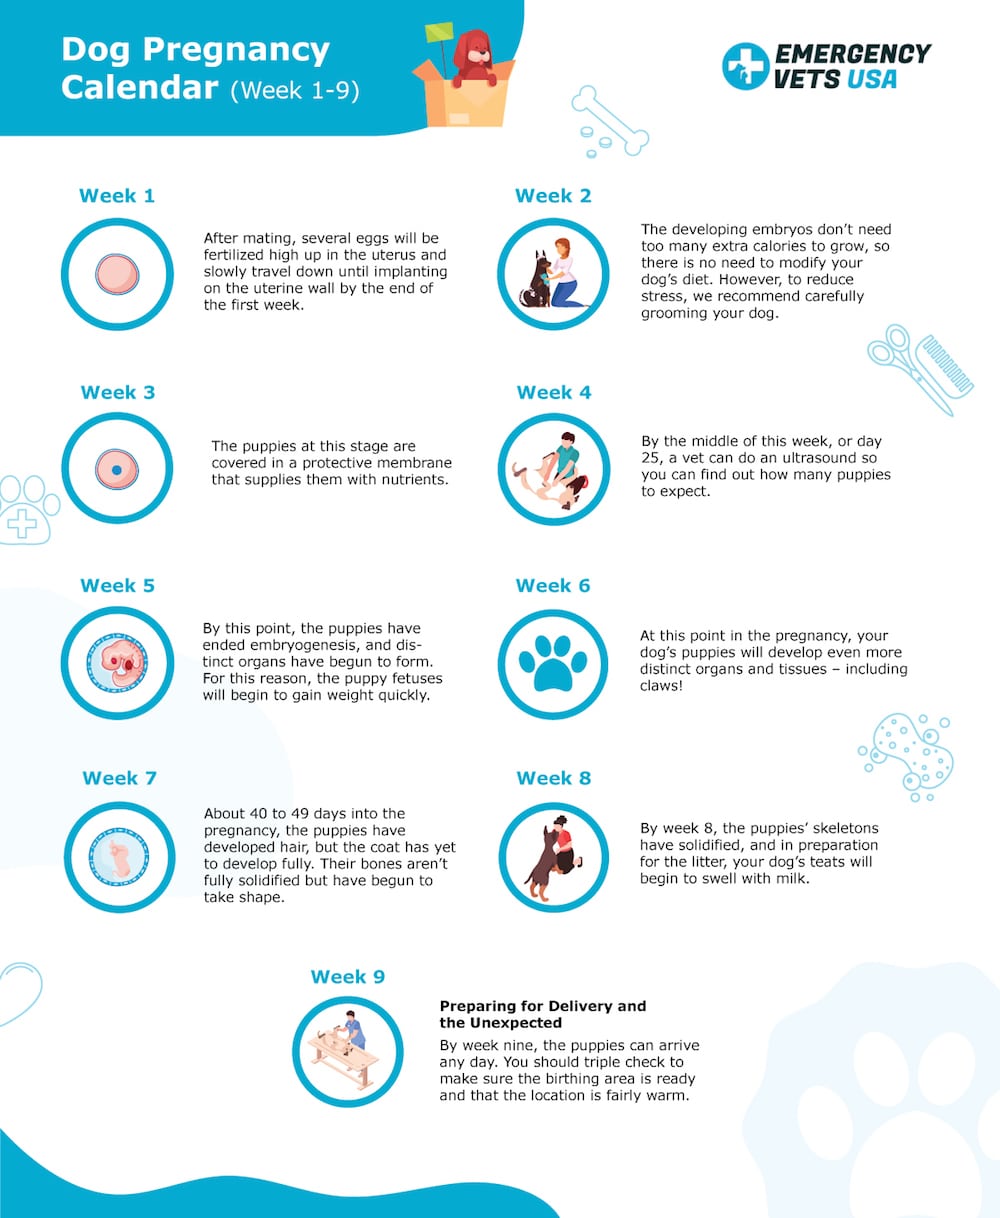

Dog Pregnancy Calendar Find Out When Your Canine Is Due To Deliver

Canine Pregnancy Calendar

Padme s Canine Pregnancy Vlog Day 52 Entry 7 top, My dog is about 51 days pregnant yesterday she started a brown top, LABRADOR RETRIEVER CASSIE 52 DAYS PREGNANT top, How Long Are Dogs Pregnant Labour Gestation Period top, Dog Pregnancy Calendar What To Expect When She s Expecting top, Pregnancy Ultrasound Radiographs Conyers Animal Hospital top, Pregnancy calendar day by day top, Whelping Puppies Unexpected Early Delivery. Raising Puppies top, Week by Week Dog Pregnancy Signs for Proud Puppy Parents top, 38 Days Pregnant Dog 2024 www.gemologytidbits top, Dog Pregnancy Day by Day Timeline Stages and Tests Dog Health Guide top, The Last Week of A Great Dane s Pregnancy Dog Blog It top, My dog is showing all signs of pregnancy but xray showed no top, Canine Pregnancy Calculator and Calendar top, 12 Signs of False Pregnancy in Dogs PetHelpful top, How Long Are Dogs Pregnant Dog Gestation Period top, How Long Are Dogs Pregnant Dog Gestation Period Explained top, Abortion top, D Litter Diary top, Veterinary Sciences Free Full Text Development of Dog Immune top, Diagnosing Treating Canine Dystocia Clinician s Brief top, Canine Pregnancy Scanning West Midlands top, D Litter Diary top, French Bulldog Pregnancy Stages 9 Weeks Of Fun French Bulldog top, Dog Pregnancy Calendar Find Out When Your Canine Is Due To Deliver top, Canine Pregnancy Calendar top, Early Contractions and Labor top, Pregnancy in Dogs Dog News top, Dog Pregnancy Stages Revival Animal Health Learn More top, My dog is showing all signs of pregnancy but xray showed no top, Canine pregnancy diagnosis PPT top, How Long Are Dogs Pregnant Dog Gestation Period top, Welping box is complete 52 days pregnant westbygodvirginiacanecorso gooddogbreeder akccanecorso canecorsopuppies embark top, 5 Ways to Care for a Pregnant Dog wikiHow top, Dog Pregnancy Day by Day Timeline Stages and Tests Dog Health Guide top.

Padme s Canine Pregnancy Vlog Day 52 Entry 7 top, My dog is about 51 days pregnant yesterday she started a brown top, LABRADOR RETRIEVER CASSIE 52 DAYS PREGNANT top, How Long Are Dogs Pregnant Labour Gestation Period top, Dog Pregnancy Calendar What To Expect When She s Expecting top, Pregnancy Ultrasound Radiographs Conyers Animal Hospital top, Pregnancy calendar day by day top, Whelping Puppies Unexpected Early Delivery. Raising Puppies top, Week by Week Dog Pregnancy Signs for Proud Puppy Parents top, 38 Days Pregnant Dog 2024 www.gemologytidbits top, Dog Pregnancy Day by Day Timeline Stages and Tests Dog Health Guide top, The Last Week of A Great Dane s Pregnancy Dog Blog It top, My dog is showing all signs of pregnancy but xray showed no top, Canine Pregnancy Calculator and Calendar top, 12 Signs of False Pregnancy in Dogs PetHelpful top, How Long Are Dogs Pregnant Dog Gestation Period top, How Long Are Dogs Pregnant Dog Gestation Period Explained top, Abortion top, D Litter Diary top, Veterinary Sciences Free Full Text Development of Dog Immune top, Diagnosing Treating Canine Dystocia Clinician s Brief top, Canine Pregnancy Scanning West Midlands top, D Litter Diary top, French Bulldog Pregnancy Stages 9 Weeks Of Fun French Bulldog top, Dog Pregnancy Calendar Find Out When Your Canine Is Due To Deliver top, Canine Pregnancy Calendar top, Early Contractions and Labor top, Pregnancy in Dogs Dog News top, Dog Pregnancy Stages Revival Animal Health Learn More top, My dog is showing all signs of pregnancy but xray showed no top, Canine pregnancy diagnosis PPT top, How Long Are Dogs Pregnant Dog Gestation Period top, Welping box is complete 52 days pregnant westbygodvirginiacanecorso gooddogbreeder akccanecorso canecorsopuppies embark top, 5 Ways to Care for a Pregnant Dog wikiHow top, Dog Pregnancy Day by Day Timeline Stages and Tests Dog Health Guide top.